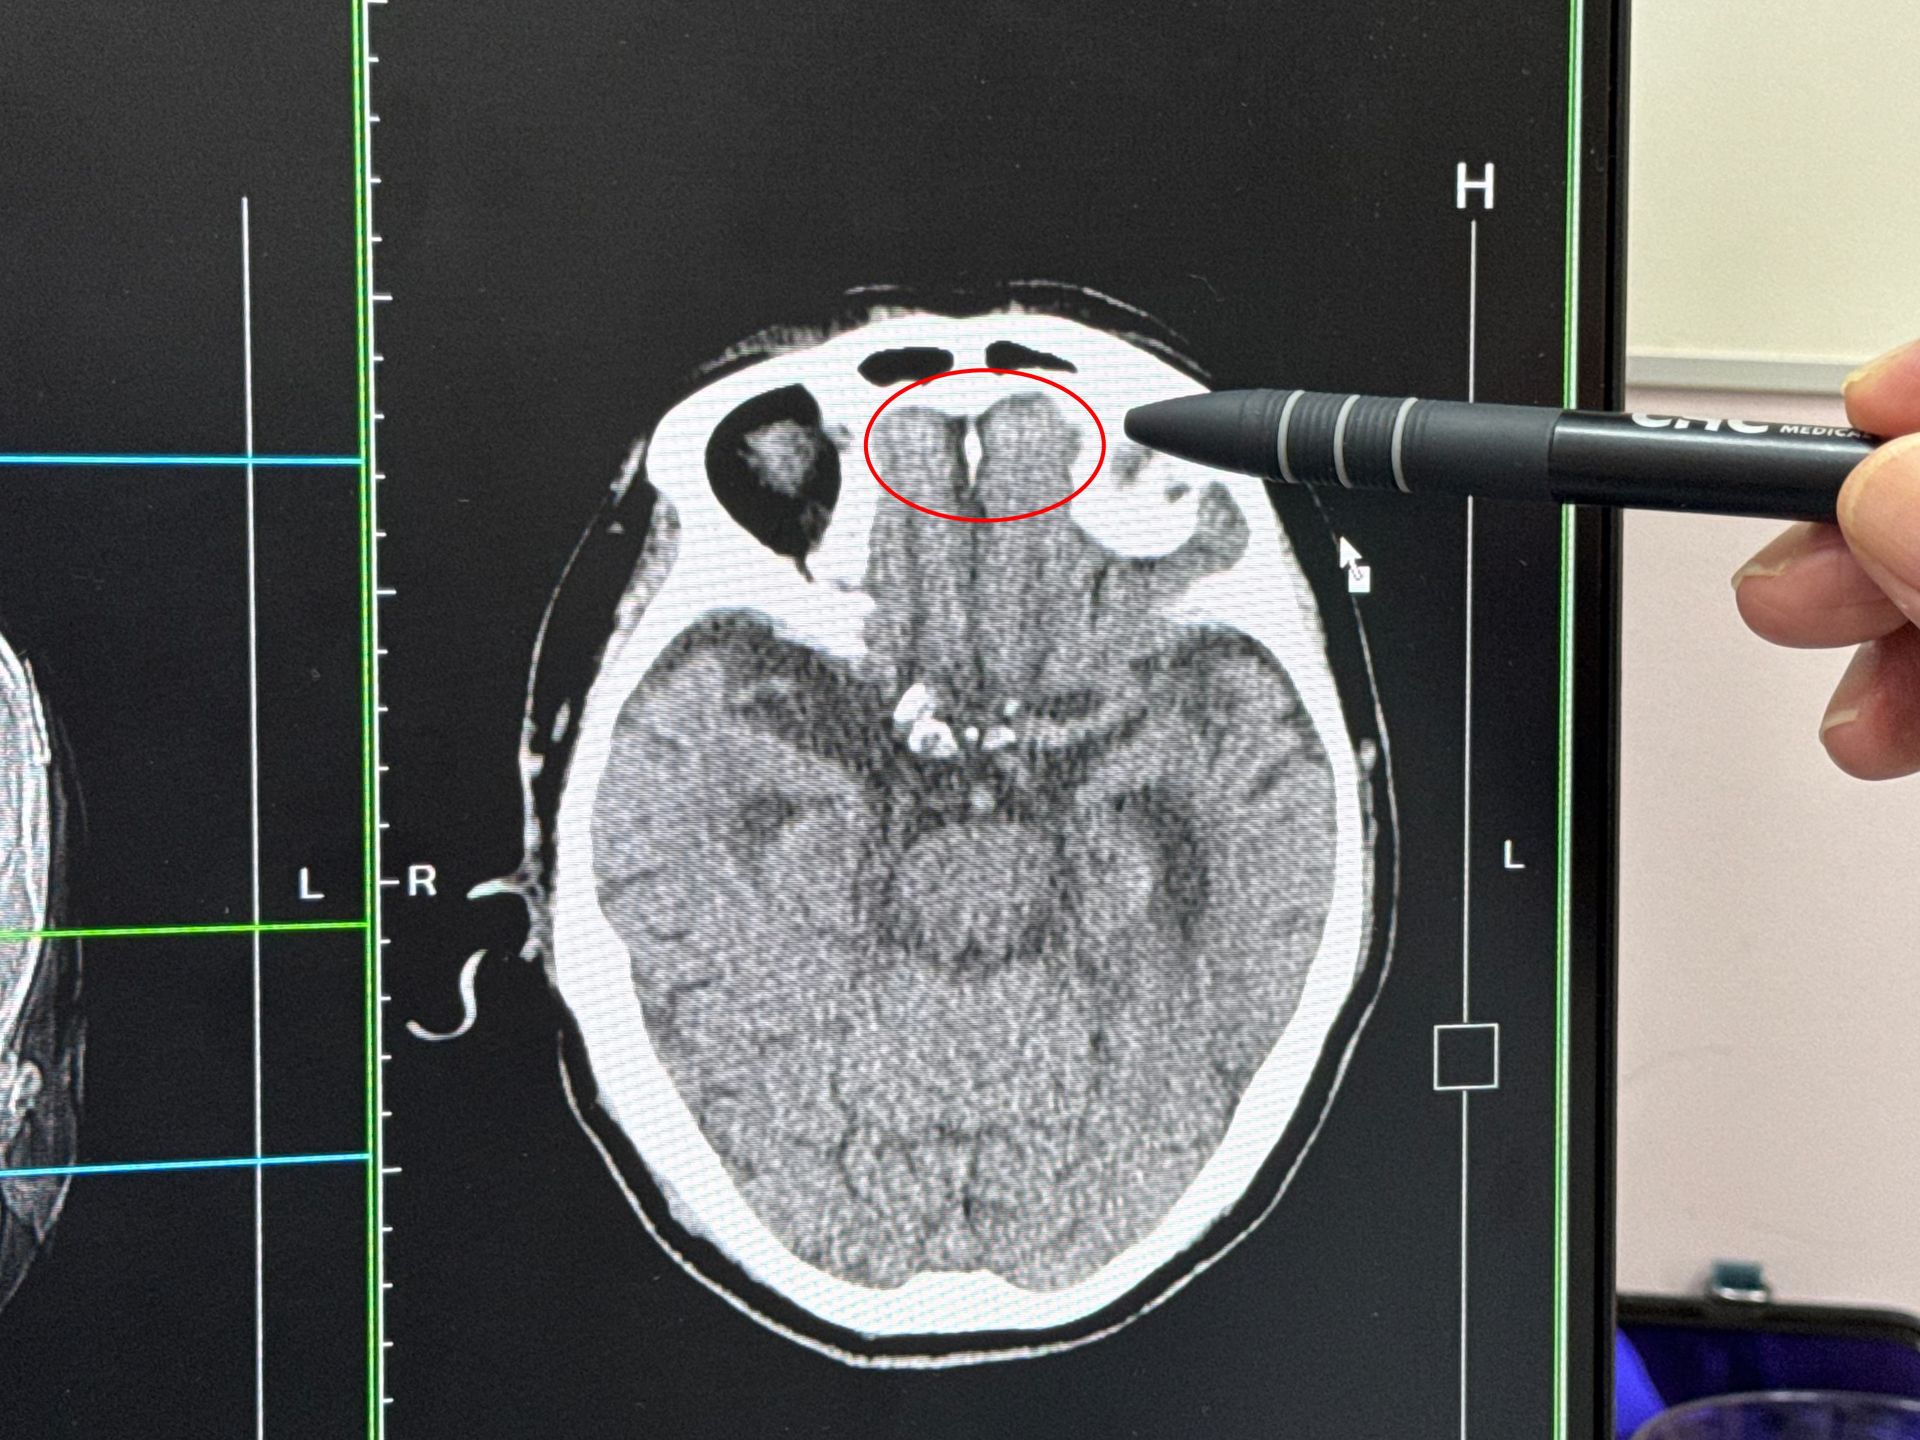

一名9旬老翁牽機車跌倒,導致右額葉腦出血。大甲李綜合提供

李綜合醫院總院長、神經外科主治醫師李旭東表示,該患者自述,在家中騎樓牽機車時摔倒,頭部當場著地,流了很多血,被救護車送到醫院急診,清洗傷口後,發現有一個4公分及一個1公分的撕裂傷,右膝蓋也擦傷,頭部縫了10多針,由於撞擊力道很大,進一步檢查確認顱內右額葉腦輕微出血,馬上安排住院治療。

李旭東說,該患者去年才因顱內出血手術開刀治療,休養後逐漸康復,能行動自如,沒想到這次卻因為疏忽,在家中跌倒,不只頭部有撕裂傷,甚至還顱內出血,所幸出血量不多,也沒有傷及其他部位,給予止血及藥物治療。